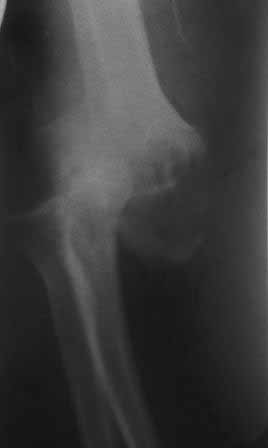

Пациент 45 л. Обратился к нашему доктору с жалобами на боли и ограничение движений в правом локтевом суставе, под углом 140гр., движения качательные, болезненные.

Травму получил 7 месяцев назад. Д-з " застарелый задненаружный вывих предплечья"

Всем доброго времени. Относительно тактики лечения... У нас был подобный случай застарелого вывиха предплечья в сочетании с переломом наружного мыщелка плеча. Оперировали через 6 месяцев после травмы. Доступ был с отсечением локтевого отростка. После операции фиксировали спицами через локтевой отросток на 3 недели. На сегодня прошло 6 лет. Сгибание у больной полное, разгибание 170 градусов. Болевого синдрома нет.